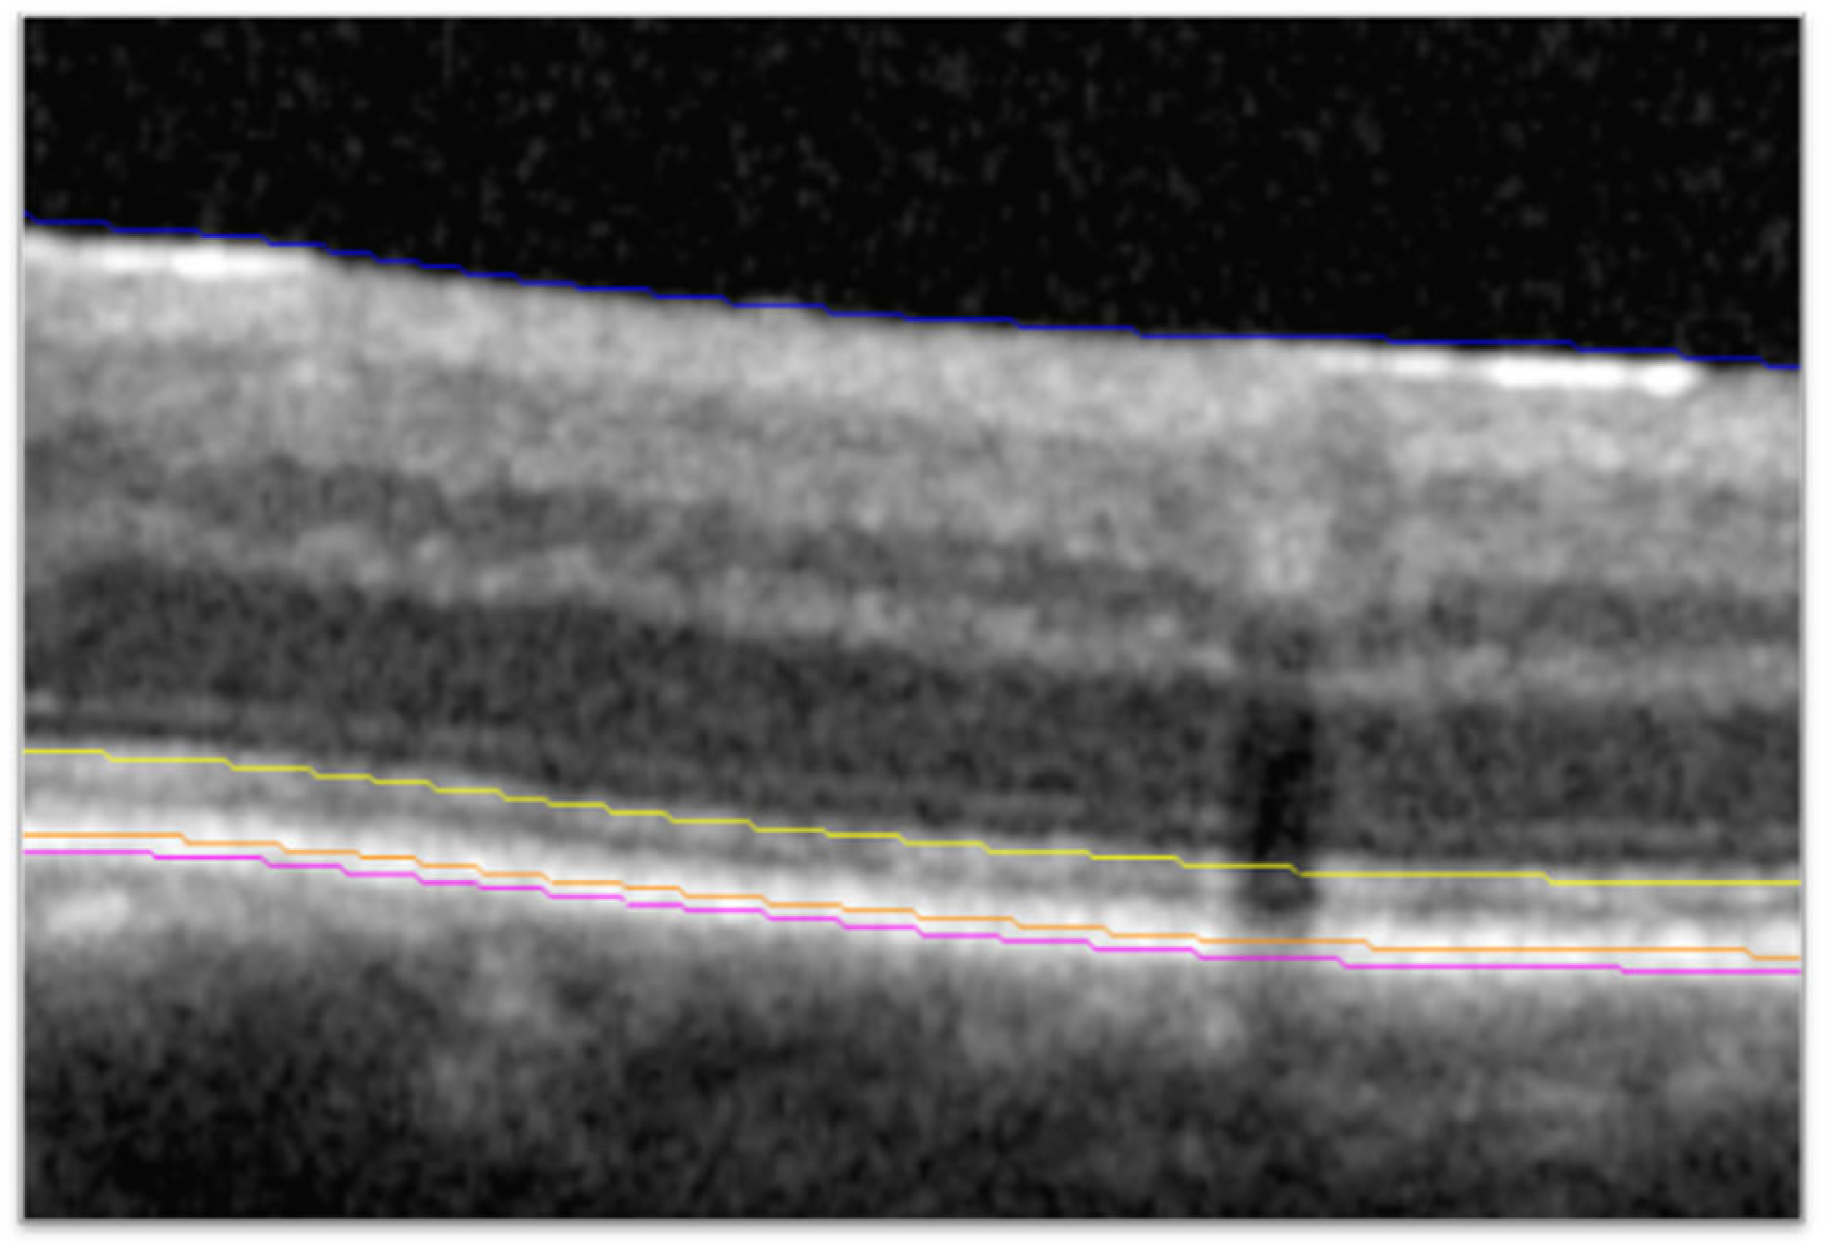

2.2. Higher-Order Optical Coherence Tomography Analysis